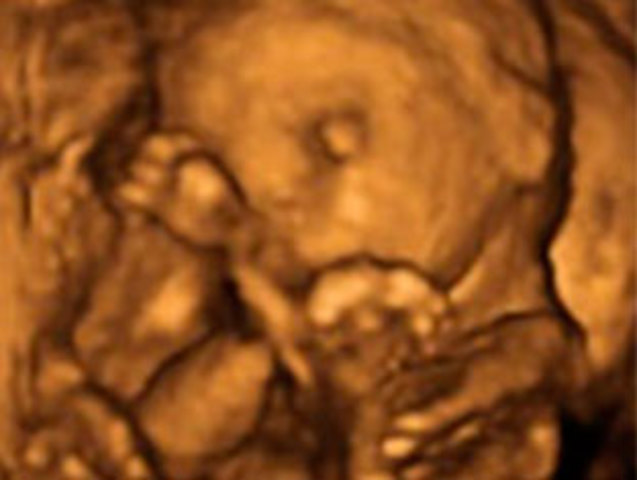

Los párpados del niño se abren y se pueden ver los ojos. La lengua sale de la boca y se mueve hacia los lados. Tu hijo bosteza, sonríe y empieza a hacer gestos como si de un niño mayor se tratase. Actualmente ya hay estudios que confirman que los bebés de esta edad gestacional… ¡incluso sueñan dentro del útero materno!

En este momento el feto tiene sus ciclos de sueño y de vigilia. Es decir, pasará grandes ratos durmiendo y no le notarás moverse. Y sin embargo, en otros momentos del día el movimiento será muy evidente.